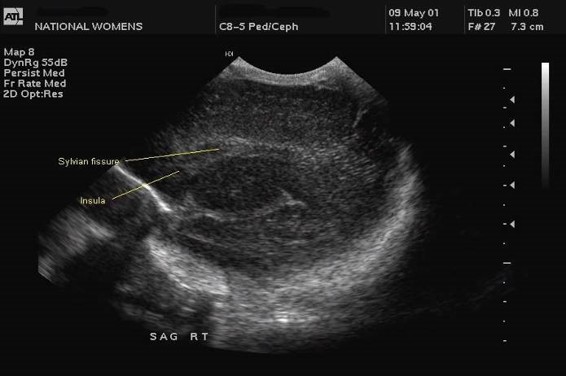

The Ventricular index, as described by Levine, is the absolute distance between the falx and the lateral wall of the anterior horn in the coronal plane at the level of the third ventricle. Values more than 4mm above the 97th centile for gestational age are indicative of significant ventricular dilatation (see chart). A study by Brouwer et al compared early CSF drainage, at a ventricular index of 4 mm above the 97th centile, to drainage beyond this threshold, and showed that early treatment was associated with better development quotient at 2 years and a decreased likelihood of shunt dependence; there was, however, no reduction in the rate of cerebral palsy with early drainage.